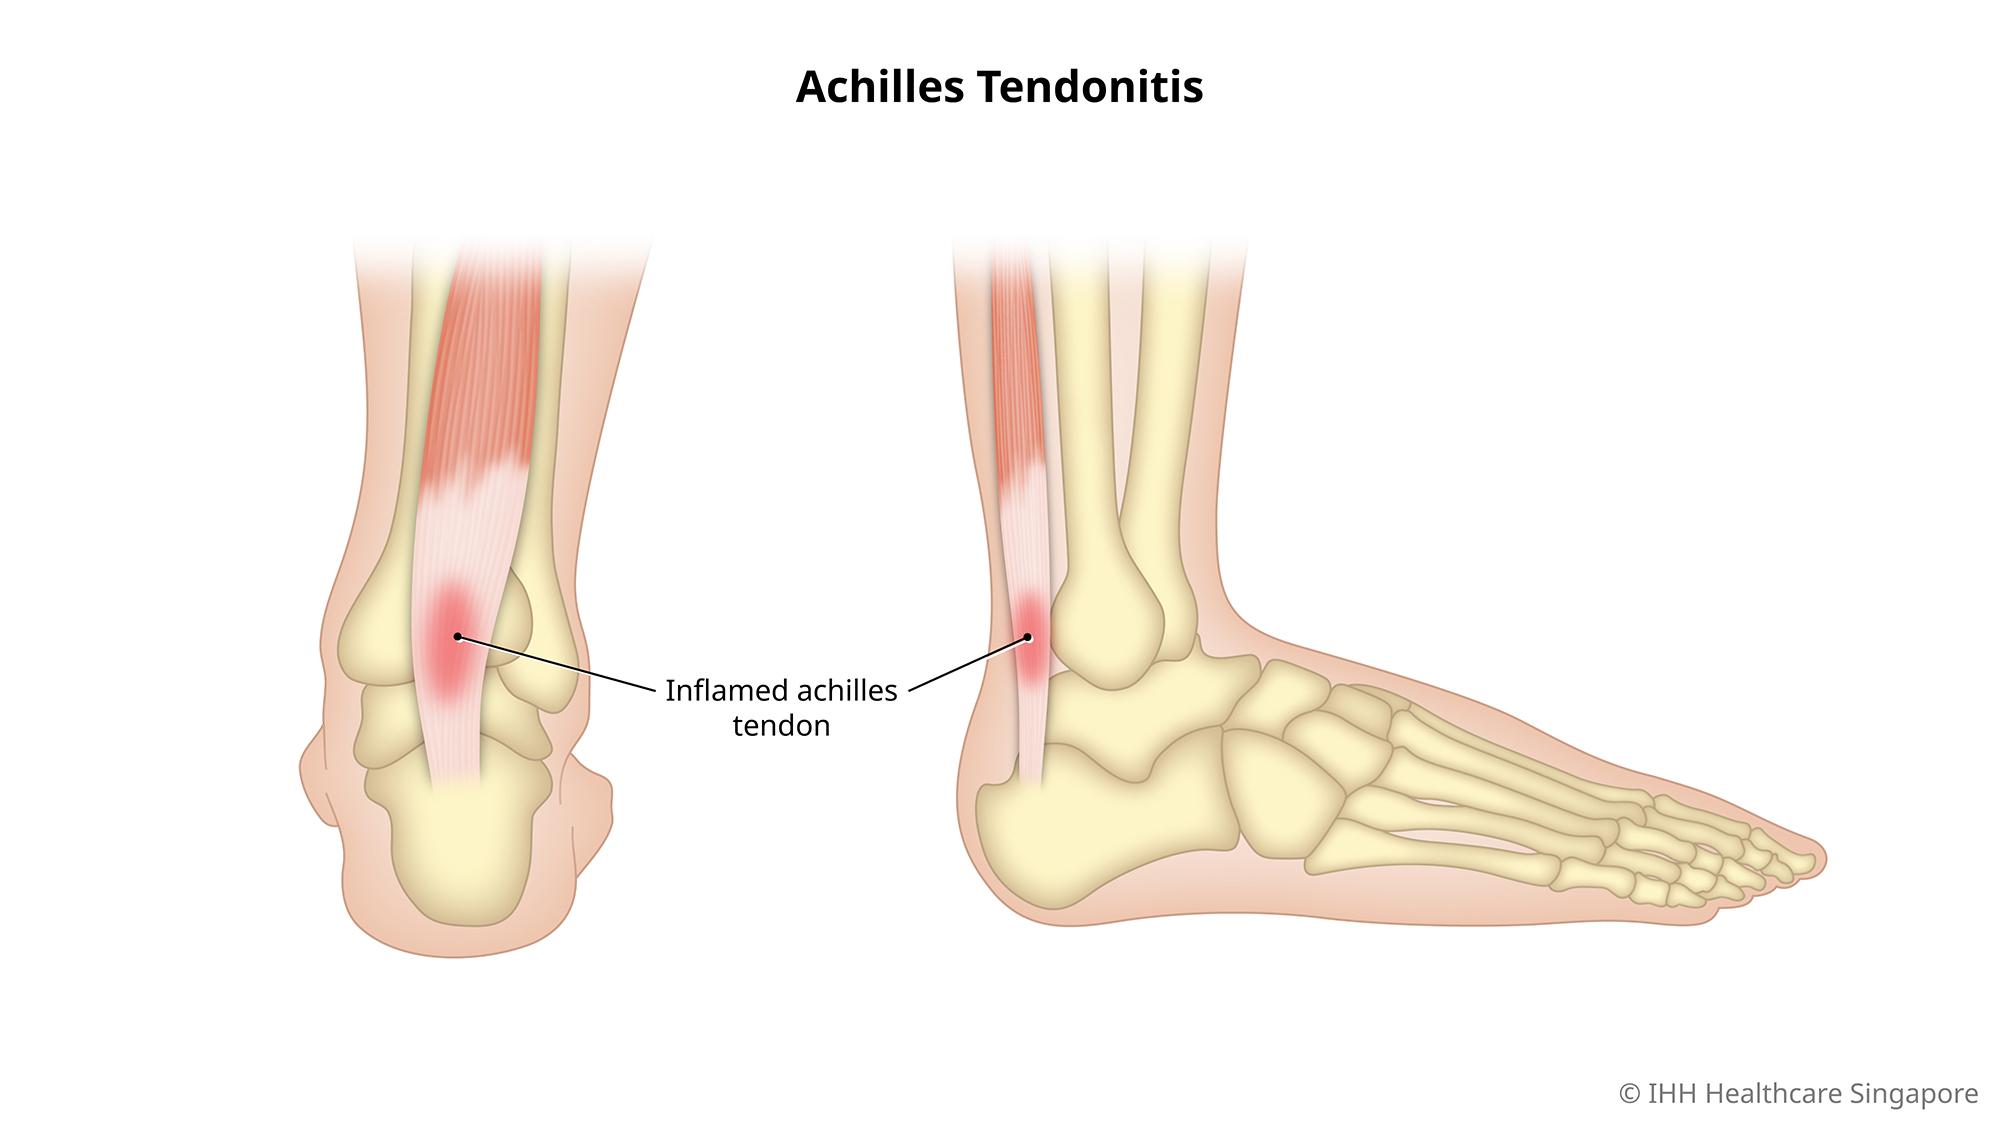

Product Item: Swollen achilles tendon treatment dealsAchilles tendon injuries healthdirect deals, Achilles Tendinitis Symptoms Treatment deals, How to Relieve Achilles Tendonitis in SECONDS deals, Achilles Tendinitis OrthoInfo AAOS deals, Achilles Tendinitis Exercises to Heal and Strengthen Your Tendon deals, Achilles Tendon Pain Causes Treatments Prevention deals, Achilles tendon Overview Mayo Clinic Orthopedics Sports Medicine deals, Achilles Tendonitis Symptoms and Treatment Caruso Foot and Ankle deals, Tendinopathy Symptoms Causes Treatment deals, Achilles Tendinitis OrthoInfo AAOS deals, Chronic Achilles Tendon Pain Diagnosis Treatment HSS deals, Know the Symptoms of Achilles Tendonitis Tendinopathy Gait Happens deals, Achilles tendinopathy Symptoms causes and treatment Bupa UK deals, Achilles Tendon Injuries deals, Swollen Achilles tendon Why does it swell and when can I exercise deals, Heal Your Achilles Tendonitis At Home Achilles Tendon Treatment deals, Achilles Tendonitis FootEducation deals, Achilles Tendinopathy Symptoms Treatments Recovery deals, Achilles Tendinopathy Causes Symptoms Treatment The Feet People Podiatry deals, How to fix Insertional Achilles Tendonitis deals, Achilles tendinitis Symptoms causes Mayo Clinic deals, Back of Achilles Tendon Heel Pain Shoes Orthotics Home Treatment deals, Achilles Tendonitis Causes Symptoms Signs Gleneagles Hospital deals, Achilles Tendinopathy NHS Lanarkshire deals, Achilles Tendinitis in Children Causes and Treatment deals, Achilles Tendonitis Common Symptoms Diagnosis and Treatment deals, Achilles Tendinitis Types Symptoms Causes Diagnosis Treatment and More deals, Achilles Tendinitis River Forest Rheumatoid Arthritis Elmhurst deals, Achilles tendinopathy is when you have micro tears in the tendon deals, Achilles swelling sales pain deals, Achilles Tendon Burning Pain Treatment Achilles Tendonitis deals, Achilles Tendinopathy Causes Symptoms Treatment The Feet People Podiatry deals, Exercises for Achilles pain Three gentle moves to get your rehab going deals, Achilles Tendinosis Treatment Symptoms and More deals, Achilles deals tendon swelling deals.